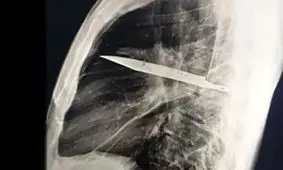

در یکی از نادرترین موارد پزشکی ثبتشده، مردی ۴۴ ساله اهل تانزانیا با ترشح چرک از قفسه سینهاش به اورژانس مراجعه کرد؛ اما آنچه پزشکان کشف کردند، فراتر از انتظار بود.